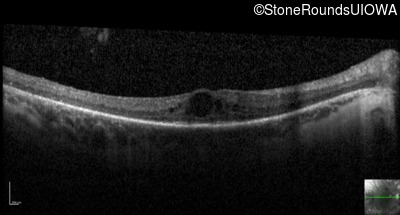

Optical Coherence Tomography - Left - 20/80 +2

Exemplar / OCT Stack